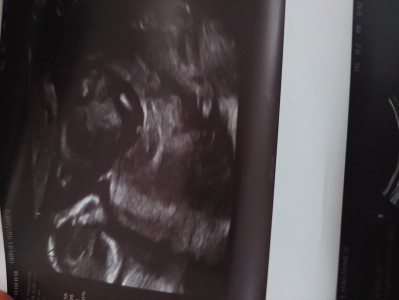

Bilgili anneler yorum yapabilir misiniz

Rahatı yerinde maşallah erkeğe benzettim cinsiyeti erkek mi ?

13 haftalik erkek  dedi 1 hafta sonra gittim kiz dedi ne oldugunu bende bilmiyorum muallakta kaldim

16-17 haftada net söyler zaten, bence erkek ama sağlıkla al kucağına

Orda bir Bebek var onu söyleyebilirim ama sadece o kadar

Crl kac canim

Crl bebeğin popo baş mesafesi değil mi ?

Anlamiyorum ama tamamen sallayarak erkek bebek diyorum :)